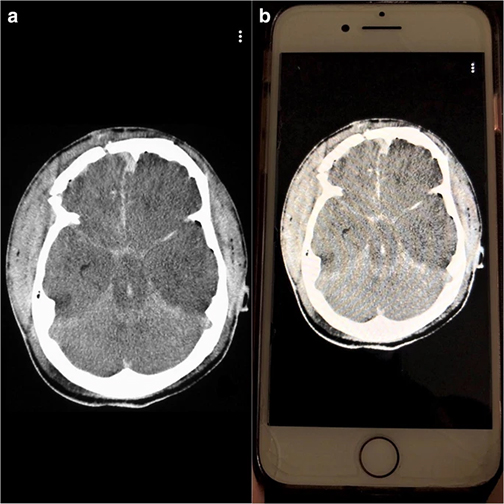

The team compared image analysis and interpretation by radiology residents using Snapchat on smartphones with conventional analysis on a single screen in the resident conference room.

“All cases used were diagnoses considered to require emergent, non-routine communication on the order of minutes to the ordering health care provider,” notes Bradley Spieler, MD, Vice Chairman of Research in the Department of Radiology at LSU Health New Orleans School of Medicine. “As such, these types of diagnoses demand prompt imaging recognition as they are considered critical findings which could result in death or significant illness if not acted upon expeditiously.”The team chose Snapchat, a social media app allowing communication via video and digital images with text messaging functionality, not only because of its popularity with young adults, but most importantly because unlike other image based social media platforms, Snapchat allows for the timing of image visibility by users. The ability to specify the length of time an image is visible to a user (or trainee in this scenario) in rendering an image-based diagnosis creates an intriguing potential for innovation in radiologic curricula, particularly as it relates to assigning a metric to diagnostic performance.

“All residents performed better on Snapchat each week,” says Dr. Spieler, who is also an Associate Professor of Radiology, Internal Medicine, Urology, & Cell Biology and Anatomy at LSU Health New Orleans. “Their accuracy rate was higher using Snapchat than a traditional classroom screen.”

Spieler says, “We believe that the results from this pilot study could facilitate a promising and novel training method in enhancing recognition of imaging diagnoses, particularly those of life-threatening nature, which could be applied to the evolving landscape of distance learning.”